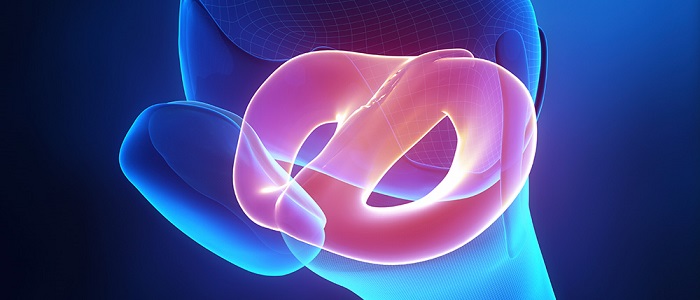

Vücutta, uyluk kemiği ve bacakların eklemler sayesinde meydana getirdiği bölgeye diz eklemi adı verilir. Kıkırdaklardan oluşmuş bu dokulara menisküs ismi verilir. Diz eklemi vücut ağırlığına ve uygulanan basınçlara karşı dayanıklı bir bölgedir. Ancak bu bölge üzerinde oluşan zedelenmeler, kişilerin yaşam kalitesini ciddi oranda düşürmektedir.

Vücutta, uyluk kemiği ve bacakların eklemler sayesinde meydana getirdiği bölgeye diz eklemi adı verilir. Kıkırdaklardan oluşmuş bu dokulara menisküs ismi verilir. Diz eklemi vücut ağırlığına ve uygulanan basınçlara karşı dayanıklı bir bölgedir. Ancak bu bölge üzerinde oluşan zedelenmeler, kişilerin yaşam kalitesini ciddi oranda düşürmektedir.

Menisküsün ana görevi; öne-arkaya dönme hareketlerinde vücudun sabit durmasını sağlamaktır. Bunun dışında üstten ve alttan gelen kuvvetlerin kemiğe iletilmesi görevini üstlenmektir. Menisküsler, diz ekleminde yer alan ve “C” şeklinde olan yapılardır. İç ve dış olmak üzere iki adettir. Bu yapılar dizin stabilitesini ve süspansiyonunu sağlarken, aynı zamanda kıkırdak yapının da korunması görevini üstlenmektedir.